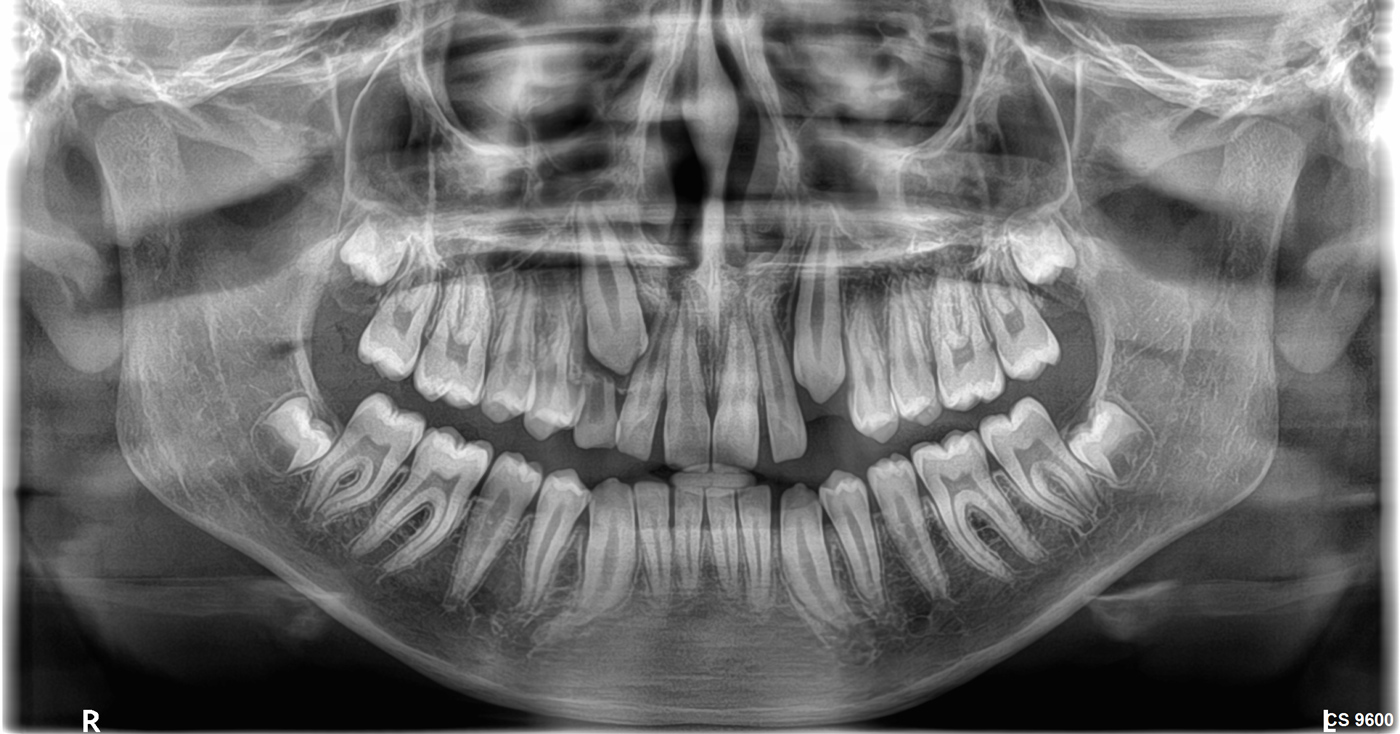

- Άριστη ψηφιακή Πανοραμική ακτινογραφία (2D).